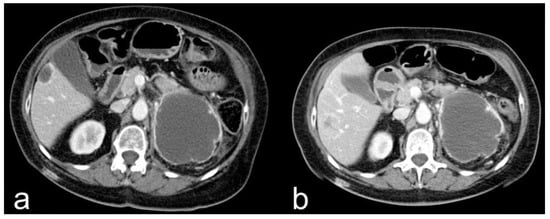

- Complete response (CR): disappearance of all target lesions together with any pathological lymph nodes (target or non-target) with short axis < 10 mm (Figure 1).